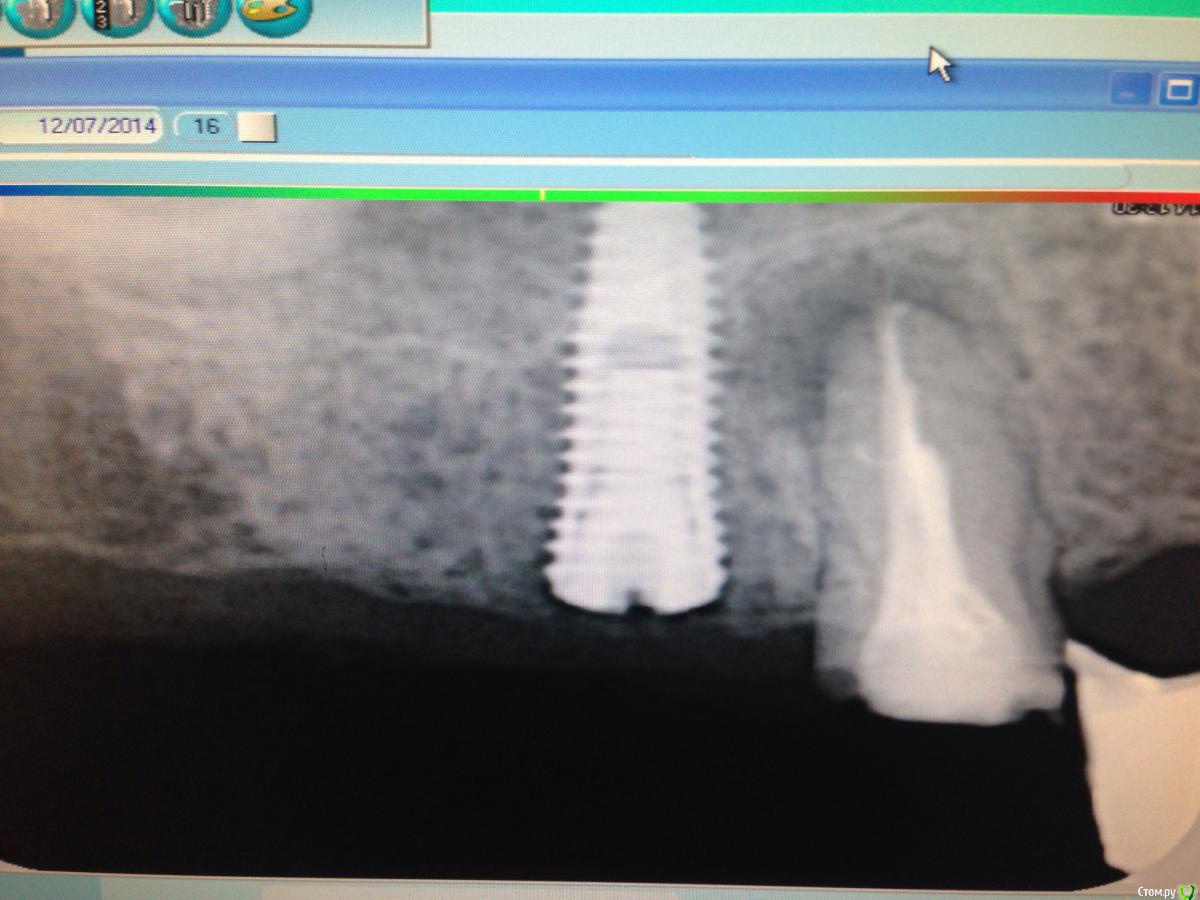

Дмитрий Никитюк Опубликовано 24 декабря, 2014 Поделиться Опубликовано 24 декабря, 2014 Одна из самых экстремальных моих работ с бикортикальной фиксацией. С костью контактирует не более 5 мм имплантата по длине:http://i008.radikal.ru/1412/4b/9957b0eee708.pngКстати, посмотрел сегодня, уже почти 6 лет, всё о.к. 5 Ссылка на комментарий

Дмитрий Никитюк Опубликовано 25 декабря, 2014 Поделиться Опубликовано 25 декабря, 2014 Для бикортикальной было бы здорово, если бы выпускали импл.с фрезерованной или полированной верхушкой, в соответствии с методикой. Это бы исключило иски пациентов о причинении вреда здоровью.Потом ознакомить с бикортикальной методикой лоров, чтобы не паниковали и не сдавали имплантологов и разработать методику гайморотомии с бикортикально установленными имплантатами - мало ли, вдруг гайморит случится через 5 лет после импл.Я буду консерватором, пока движений в этом направлении нет.Не делать то что считаешь нужным, потому что кто-то может это не правильно трактовать? НЕ, это не для меня, мне тогда вообще половины того что делаю прийдётся не делать.С лориками непонятки бывают часто, но после 5-ти минутной беседы они пасуют обычно. Умничать перед пациентом это одно, а выдержать интеллектуальную дуэль с квалифицированным специалистом это совсем другое. Заканчивается признанием осведомлённости в возможностях современной диагностики и лечения, а также признанием отсутствия современного оборудования. В наших реалиях, к сожалению, лоры пока находятся в пещерном веке, по сравнению с имплантологами. Да что там лоры, тут стоматологи по соседству отговаривают пациентов от имплантации... Что касается вдруг случится, то нужно иметь аргументы для подобных пациентов и лоров. У меня есть. Обычно начинаю с демонстрации снимка и вопроса, что видите, уважаемый коллега, и что нужно делать с пациентом в данном случае. И тут они сами всё понимают...А вот собственно и снимок:http://s50.radikal.ru/i130/1412/04/04dd63d3d7c7.png Ссылка на комментарий

АнтонТЛТ Опубликовано 25 декабря, 2014 Поделиться Опубликовано 25 декабря, 2014 А через сколько был сделан снимок после имплантации? Ссылка на комментарий

Дмитрий Никитюк Опубликовано 25 декабря, 2014 Поделиться Опубликовано 25 декабря, 2014 А через сколько был сделан снимок после имплантации?Через 5 лет. Но это значения не имеет. Ссылка на комментарий